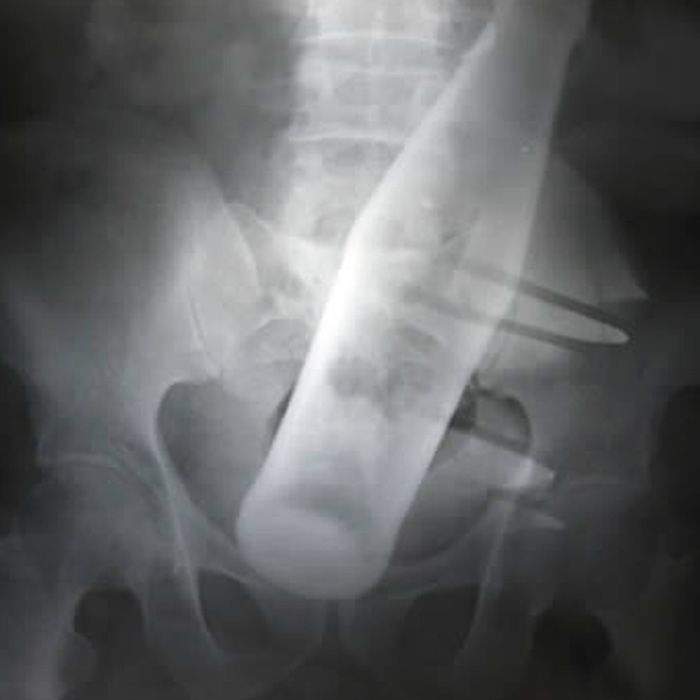

▼一個瓶子

圖片來自:ems1